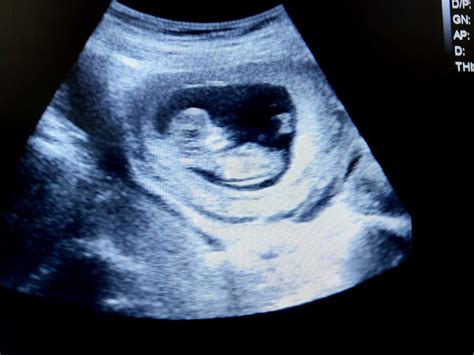

• 11 week baby ultrasound